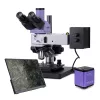

Digitální fluorescenční mikroskop MAGUS Lum VD500L (100-400x) je špičkové zařízení pro fluorescenční mikroskopii, mikroskopii ve světlém poli a fázový kontrast v procházejícím světle. Díky invertované konstrukci je ideální pro studium vzorků v laboratorních nádobách (Petriho misky, baňky) s výškou až 165 mm a tloušťkou dna 1,2 mm. Tento mikroskop najde uplatnění v medicíně, farmakologii, biochemii nebo epidemiologii.

Mikroskop je vybaven fluorescenčním LED osvětlením (5 W) s životností 50 000 hodin a třemi excitačními filtry: DAPI, FITC a TRITC. Pro světlé pole a fázový kontrast slouží 5W LED procházející osvětlení s možností nastavení pomocí Köhlerovy osvětlovací soustavy, která zaručuje ostrý a jasný obraz bez artefaktů.

Trinokulární hlava otočná o 180° nabízí dvě možnosti montáže: digitální fotoaparát a monitor. Rozdělení paprsku je 100/0 nebo 50/50, což umožňuje současné sledování vzorku a jeho záznam. Revolverový nosič má šest slotů a je osazen šesti rovinnými achromatickými objektivy (pro světlé pole, fluorescenci i fázový kontrast) s dlouhou pracovní vzdáleností.

Součástí sestavy je digitální fotoaparát MAGUS CLM90 s 7,1 Mpx monochromatickým CMOS snímačem SONY Exmor, který zajišťuje nízký šum a vysokou citlivost na světlo. Snímá v rozlišení 3200x2200 px a poskytuje plynulé video 51,3 fps při plném rozlišení a 133,8 fps při nižším rozlišení, což je ideální pro sledování pohybujících se vzorků. Peltierův článek chlazení minimalizuje tepelný šum při dlouhých expozicích.

Tento fluorescenční digitální mikroskop je perfektní volbou pro profesionální laboratoře, výzkumné instituce a univerzity.